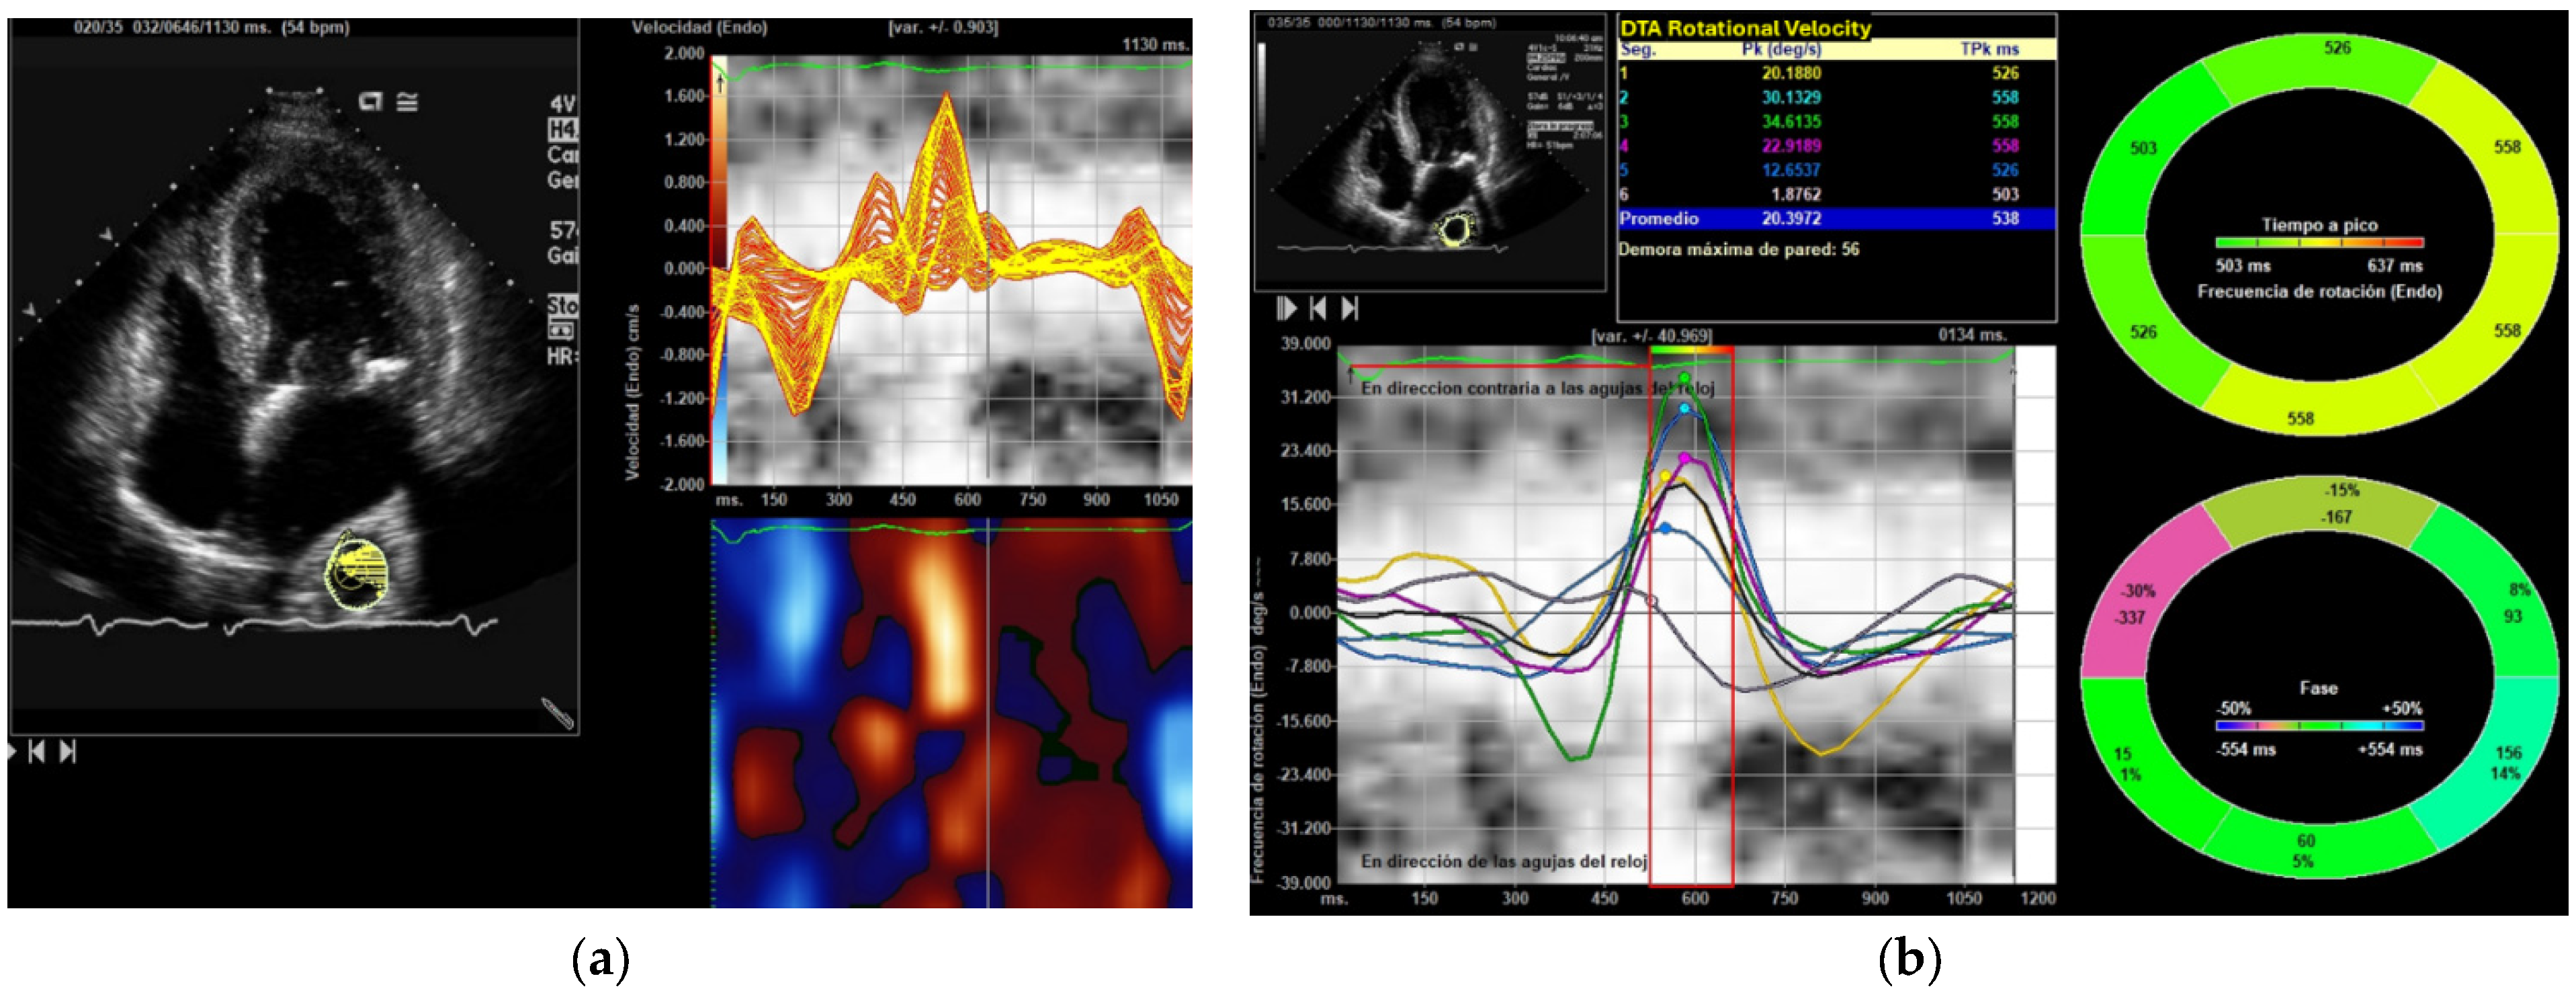

2.7. Image Acquisition and Processing

| DTA Rotational velocity (°/s) | 54.44 ± 11.22 | 107.39 ± 0.19 | <0.001 |

| DTA Radial Velocity (cm/s) | 1.18 ± 0.34 | 2.21 ± 0.27 | <0.001 |

| DTA Circumferential Strain (%) | −10.23 ± 0.45 | −11.86 ± 0.07 | N.S. |

| DTA Strain Rate Circumferential (1/s) | −1.67 ± 0.56 | −1.91 ± 0.25 | N.S. |

| DTA Rotational displacement (°) | 7.38 ± 1.87 | 15.71 ± 0.13 | <0.001 |

| DTA Radial displacement (mm) | 0.99 ± 0.32 | 1.58 ± 0.15 | <0.022 |